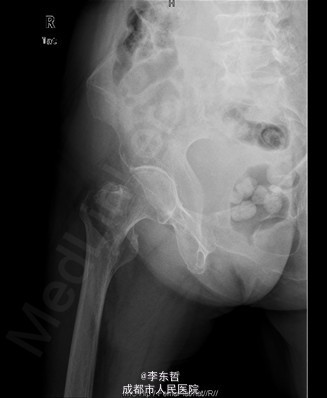

查体:T:37.2oC,P:72次/分,R:18次/分,BP:124/68mmHg。神志清楚,急性病容,皮肤巩膜无黄染,全身浅表淋巴结未见肿大。。颈静脉正常。心界正常,心律齐,各瓣膜区未闻及杂音。胸廓未见异常,双肺叩诊呈清音,双肺呼吸音清,未闻及干湿啰音及胸膜摩擦音。腹部外形正常,全腹柔软,无压痛及反跳痛,腹部未触及包块,肝脏肋下未触及,脾脏肋下未触及,双肾未触及。双下肢无水肿。 专科查体见:右髋关节局部肿胀,周围无红肿、皮肤损伤、溃疡和糜烂,右下肢短缩畸形,无表浅静脉曲张。右转子间轻触痛,扣痛。右髋活动受限,右下肢短缩畸形约5cm,轻度外旋、内收。右髋关节屈伸、外旋内旋、外展内收功能障碍。 X线片示:右股骨转子间骨折,累及大小转子,断端稍分离,未见明显错位,周围软组织肿胀明显,右髋关节在位。

初步诊断:1、右股骨转子间骨折(Evans III型);2、骨质疏松症。 诊疗计划:1、向患者及家属交待病情及注意事项。2、向上级医生汇报患者病情。3、完善术前相关检查。4、给予皮肤牵引、抬高患肢等对症处理。5、拟手术治疗。6、密切观察病情变化,根据病情及时处理。